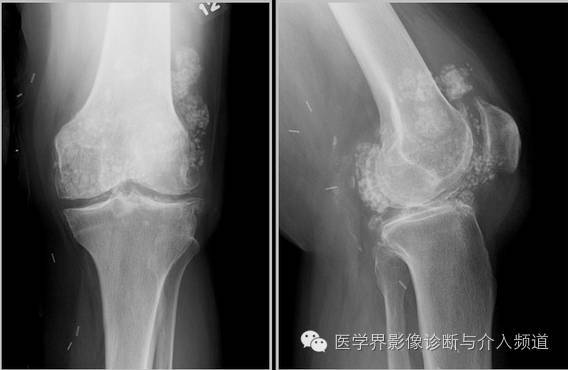

本病主要累及软骨内成骨的骨骼,特别是四肢骨,表现为透明软骨的变性坏死及伴随的吸收、修复性变化。软骨细胞常见凝固性坏死,细胞核固缩、碎裂、溶解消失后,残留红染的细胞影子。进而残影消失,基质红染,成为灶状、带状的无细胞区。坏死区还可进一步崩解、液化?;邓涝钪芪Т婊畹娜砉窍赴S蟹从π栽錾?,形成大小不等的软骨细胞团(图6)。在邻近骨组织处,坏死部位可发生病理性钙化;初级骨髓的血管和结缔组织侵入坏死灶内,出现机化、骨化,最终为骨组织软骨坏死以累及成熟中的软骨细胞(肥大软骨细胞)为主,呈现近骨性分布?;邓览┐笫?,也会波及其他层次的软骨细胞。坏死灶常为多发性,大小不一,呈点状、片状或带状。

(2)骺板软骨病变:

骺板软骨的坏死主要发生于肥大细胞层,重者可贯穿骺板全层。骺板深层发生坏死后,该部由干骺端来的血管不能侵入,正常的软骨内成骨活动停止;但坏死灶上方存活的增生层软骨细胞还能继续增生、分化,导致骺板的这一局部增厚。在坏死灶的近骨边缘常发生退行性钙化,并可沿坏死灶的干骺端沉积骨质,形成不规则的骨片或横骨梁,表示正常骨化过程停顿。而骺板的其他部分成骨活动仍在继续,因而造成骺板的厚薄不均和骨化线的参差不齐。

当坏死灶贯穿整个骺板时,由骺核和干骺端两个方向进行坏死物的吸收、机化和骨化,终于导致骺板提前骨性闭合,该管状骨的纵向生长早期停止,造成短指(趾)或短肢畸形。

由于干骺端血管丰富,骺板软骨坏死后的吸收、机化和骨化发展较为迅速,因而其X线影像在较短时间(数月至1年)内可明显加重或好转愈复。

(3)关节软骨病变:

关节面软骨也以同样的营养不良性病变开始,渐渐发生软骨破坏。关节面粗糙不平,常发生软骨溃疡,影响关节活动,诱发疼痛。部分软骨可脱落构成“关节鼠”。重症者,关节软骨边缘部增殖而呈盘状隆突,其后常有化骨,因而关节部变粗大?;ひ灿腥廾丛鲋?。绒毛脱落可成为游离体。软骨周围的滑膜也常肥厚,可构成软骨及赘骨,而致骨端更增大,边缘不规则。此外,骨质常呈普遍疏松,骨小梁破坏、吸收,可形成空泡和囊肿样结构,并可伴有增生性改变。骨质明显变薄,可疏松呈海绵状。骨髓腔扩张,髓内常出现坏死灶和空泡。肌肉、脏器和内分泌腺均伴有以营养不良性退行性变为主的病变。

和骺板软骨的坏死灶一样,关节软骨的病变也呈近骨性分布,即首先是深层成熟中的软骨细胞受累,常形成典型的带状坏死。由于此部坏死物质的吸收较为缓慢,坏死存在时间较久,故坏死灶周边部增生的软骨细胞团往往更引人注目。在较大的坏死灶当坏死物质崩解、液化后,形成裂隙或囊腔。在重力和摩擦等机械作用下,其表层软骨组织易成片剥落(分离性骨软骨炎),形成关节游离体(关节鼠),而局部关节面则留下大小不等的溃疡。重者病变部关节软骨可全层破坏消失,造成大片骨质裸露。在关节面的边缘部分,与软骨坏死相伴随常有软骨增生反应,导致关节边缘部分增厚,且可骨化而形成骨性边缘增生物(图11)。由此而引起患者骨端增大、关节变形和活动受限。后期关节滑膜结缔组织增生、钙化和骨化,更加重了关节粗大。由于关节软骨的变性坏死、崩解剥落和修复增生等过程反复进行,以致晚期病例表现为变形性关节病的改变。但从未见发生骨性关节强直。用单克隆免疫组化法显示,关节软骨表层的Ⅱ型胶原表达减少,Ⅰ型胶原增多;增生的软骨细胞团有Ⅰ、Ⅱ、Ⅲ、Ⅵ型胶原表达。

关节软骨坏死的吸收机化只能从骨板壳的正常缺口处开始,修复反应相对较弱,病变发展较为缓慢。因此,在X线下关节面(骨端)的病变往往比干骺端的病变显影较晚,修复过程发展缓慢,历经较长时间而变化甚微。